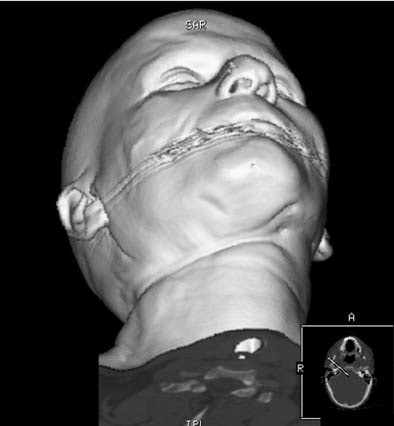

| In a suicidal hanging case, 3D CT reconstruction shows strangulation mark around the neck. Image courtesy of Dr. Michael Thali. |